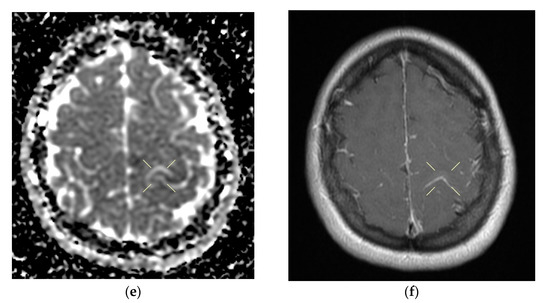

When discharged, the patient was conscious, cooperative, oriented in time and space, without stiffness in the back of the head, had no nystagmus, showed normal ocular motricity, denied diplopia, had possible deglutition for liquid and solid food, displayed symmetric facies, had no movement deficits, had no superficial tactile sensitivity or coordination disorders and showed a cutaneous plantar reflex with bilateral flexion. The images of the MRI can be seen below in Figure 4.

Figure 4. Native and contrast-enhanced cerebral MRI and angiography with arterial and venous sequencing, performed on the second day of hospitalization. The scan indicates thrombosis of the left parietal cortical vein associated with ipsilateral superior parietal subcortical venous infarction—(a) band in T2 and FLAIR hypersignal. (b) band in T2 and FLAIR hypersignal. (c) T1 hyposignal. (d) restrictive in diffusion coefficient. (e) restrictive in diffusion coefficient. (f) restrictive in diffusion coefficient with weak contrast enhancement. Demyelinating lesions are organized in the crown, radiated and parietal on the right side, most probably with an ischemic vascular sublayer. The native cranio-cerebral and post-contrast MRI examination with arterial and venous angiographic sequencing highlighted the following: normal pericerebral liquid spaces; a symmetric ventricular system, with normal dimensions; an area in the hypersignal band T2, and a FLAIR/iso-hypo signal T1, with restricted diffusion weighing, weak gadolinophilia, axial dimensions of about 9/16 mm, located subcortically and parietally on the upper left side; two millimeter focal points of the T2 and FLAIR hypersignal, with no diffusion restrictions or detectable contrast outlet organized in the crown, radiated and parietal subcortical on the right side, in the area adjacent to the dorsal horn of the VL; structures of the median line in the right position; orbits and orbital content without anomalies; paranasal sinuses with normal development and pneumatization; the absence of images evoking hemorrhagic accumulations or masses with a tumor sublayer; symmetrically disposed internal carotid arteries with normal trajectories and caliber; a normal bilateral carotid siphon with no position or extrinsic compression anomalies, with homogeneous intensity of the intralumenal signal; anterior and middle cerebral arteries that were normally detached from the internal carotid on both sides, without any areas of inferior longitudinal stenosis with an aspect within the normal limits; transverse and symmetric sigmoid sinuses, without lesions; the rest of the patient’s evaluable venous segments did not present any defect in the lumen signal.